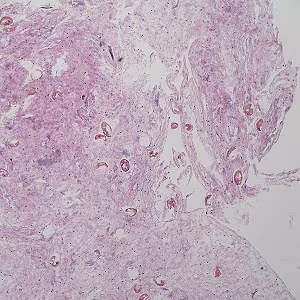

A 68-year-old female with microscopic hematuria had a cystoscopy performed. A pathologist detected objects on hematoxylin and eosin (H & E) stained slides (Figures A–E) and on Papanicolaou stained slides of urine sediment (Figures F–I). A parasitic infection was suspected and images of the objects were captured and sent to DPDx for diagnostic assistance; the objects had a size range of 75-80 micrometers. What is your diagnosis? Based on what criteria?

Figure A